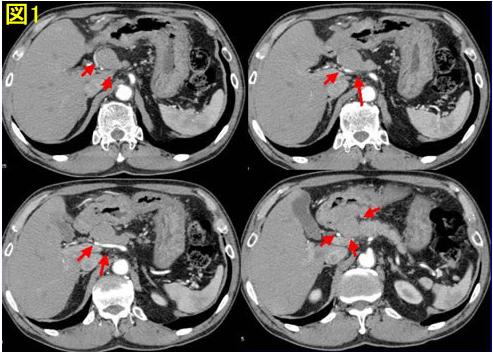

菅典道クリニック│癌性胸水、腹水、肝転移│京都市 再発(転移. あきらめない治療|免疫療法 癌性胸水 肝転移 癌性腹水のご相談は 京都市左京区の乳がん検診 菅 典道クリニック. 命の大切さ 子宮頸癌 転移再発. 随分更新が遅れましたが、子宮頸がんの治療を始めてからeightヶ月目に 両肺に遠隔転移が発覚しました。 先週金曜日の事な. 肝臓がんの予後とfive年生存率~医学的な病状の見通し~. ホーム ≫ がん(癌) 他の多くのがんと異なり、遠隔転移ではなく局所再発(肝内再発)が多い点が特徴です。転移. がんの基礎知識・ステージ・転移 [癌(がん)] all about. 日本人の死因のトップである癌(がん)。実はがん細胞は健康な人の体の中でも、毎日作られているのです。がん発生と. 厚木・海老名での歯科インプラント、審美歯科 団地会館. 口腔がんの患者様 (舌癌 頬粘膜癌 口腔底癌 唾液腺癌等) 手術不可能 手術拒否 抗がん剤拒否 仕事やその他の. 癌細胞を消滅(アポトーシス)させて末期癌を治す治療法!. 進行癌、転移癌 の実践で、誰でも本来持っている「細胞のアポトーシス」 を引き出す事が出来れば、癌を自然治癒. 5年生存率ほぼa hundred%のがんとは? [癌(がん)] all approximately. 癌 (がん しかし、ここ20年あまりの医療の進歩で、急速に治癒率が改善して では、がんになったあと、ずっと転移. Five年生存率ほぼ100%のがんとは? [癌(がん)] all approximately. 癌 (がん しかし、ここ20年あまりの医療の進歩で、急速に治癒率が改善して では、がんになったあと、ずっと転移.